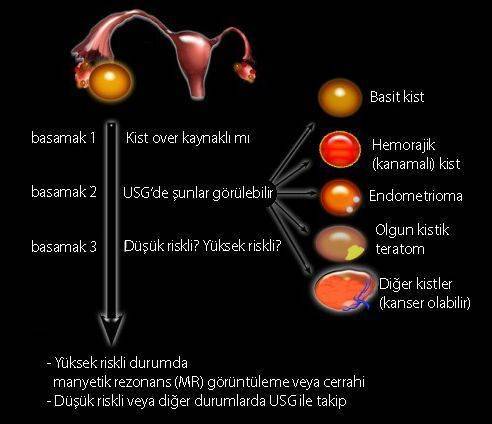

Dermoid kisti olup hamile kalanlar. Bu kist ağrılı birlikteliğe ağrılı mens dönemine kısırlığa yapışıklığa neden olabiliyor. Dermoid kisti olup hamile kalanlar. 16 mayıs 2018 hamilelikte anne sağl. 0 850 811 76 40 prof.

Kisti olup hamile kalanlar kist hamile kalmaya engelmidir kist varken hamile kalınırmı kist hamile kalmamda sorun yaratırmı kist ve gebelik hakkında bilgiler bazı kadınlar kistleri oldugu için bazen hamile kalmayabilir ancak 3 cm lik kisti olupta hamile kalan birsürü insan var. şubatta kontrole gideceğim umarım ben de hamile kalabilirim hayırlısıyla. Adet sancıları şiddetli olan derin cinsel ilişkide ağrısı olan karında ve kasıkta ağrıları bulunan kanlı dışkılama idrarda yanma ve kanama olması adet kanaması olduğunda burun kanaması olan vücudunda değişik yerlerde morluklar oluşan ve üreme çağında olan kadınların çikolata kisti açısından tehdit altında. çikolata kisti hamile kalmayı nasıl engeller.

Kisti olup hamile kalanlar. çikolata kisti olup sol tüpü kapalı hamile kalanlar çikolata kisti. Bunun opere olması şart değil. şubatta kontrolüm var dua ediyorum o zamana kadar hamile kalayım diye teşekkür ederim geçmiş olsun size de dermoid kistler ilaçla küçülmüyor maalesef benim de ilk dr görmemişti kisti alttan ultrasonla bakmasına rağmen 2.

Kizlar ankarada 2 devlet kadindogum hastanesi gezdim ama beni mahvettiler. çikolata kisti olup sol tüpü kapalı hamile kalanlar çikolata kisti. Merhaba kistler türüne göre gebe kalmada sıkıntı yaratır çikolata kisti de hamile kalmaya engel olan kistler den biri. Kistimin polikist oldugunu adet gorunce gectigini soylediler ve suan 2 yillik evliyim ozel hastane adini cok duydugum hulisi bulent zeynelogluna gittim dermoid kistimin oldugunu soyledi ameliyat oldum bugun 3.